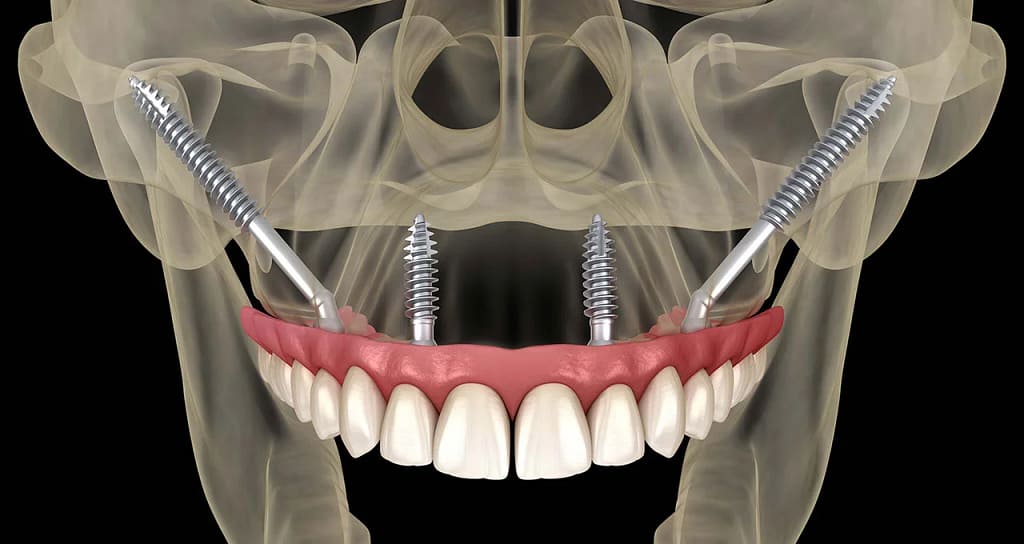

Los implantes cigomáticos son implantes de titanio que son significativamente más largos que los implantes convencionales (pueden medir entre 30 mm y 52.5 mm).

A diferencia de los implantes tradicionales, que se anclan en el hueso alveolar maxilar (el hueso donde estaban los dientes), los implantes cigomáticos se extienden y se fijan en el Hueso Cigomático (o Pómulo).

El hueso cigomático es una estructura densa y fuerte que nunca se reabsorbe, sin importar cuánto tiempo haya pasado desde la pérdida de los dientes.

En esencia: Si el suelo es demasiado blando para construir la casa, simplemente anclamos los cimientos a una roca sólida cercana.

Debido a su proximidad a estructuras críticas (como la órbita del ojo y el seno maxilar), los implantes cigomáticos son considerados una cirugía de alto nivel de complejidad. No es un procedimiento que deba ser realizado por cualquier implantólogo.

- Diagnóstico 3D Riguroso: Uso indispensable de la Tomografía Computarizada (CBCT) para mapear la anatomía tridimensional del seno y el pómulo.